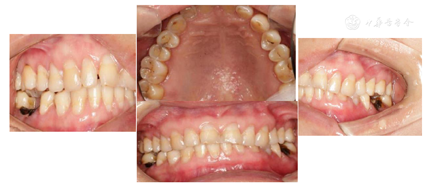

随访6个月、1年、2年,冷热酸甜刺激敏感症状明显消失,且无自发性疼痛。充填材料使用4年无脱落,无继发龋。

术后6个月、1年、2年后检查充填物完好,患者自觉满意。

大块充填树脂也可用于儿童牙科,边缘密合性优于传统金属预成冠[6]。一般根管治疗后的窝洞深度都大于4 mm,因此,目前高黏型大块充填树脂用于根充后充填时仍然是两步充填。对于深龋洞的患牙,大块充填树脂也是一个良好的选择。本病例中,患者张口度小,且多颗患牙为深龋,传统的树脂分层充填技术会延长患者的张口时间,增加医师的工作强度。虽然大块充填树脂的临床疗效有待进一步验证,但其操作简便,一次固化可达4 mm,节约了椅旁时间,具有一定的优势。一项系统评价比较了大块树脂与传统复合树脂的效果,结果显示大块树脂可有效改善边缘变色和继发龋,但是其边缘适应性有所下降[9]。本例患者随访2年,结果显示大块树脂充填有效降低了术后敏感,减少了继发龋,美学性能良好,生物学性能稳定,患者较为满意。未来,大块充填树脂应当在兼顾物理、机械性能的同时完善美学特性,提高固化深度,并向自酸蚀自黏结树脂和黏度可变型树脂方向发展,实现快捷、有效、美观、方便于一体,成为真正的一步充填通用树脂。